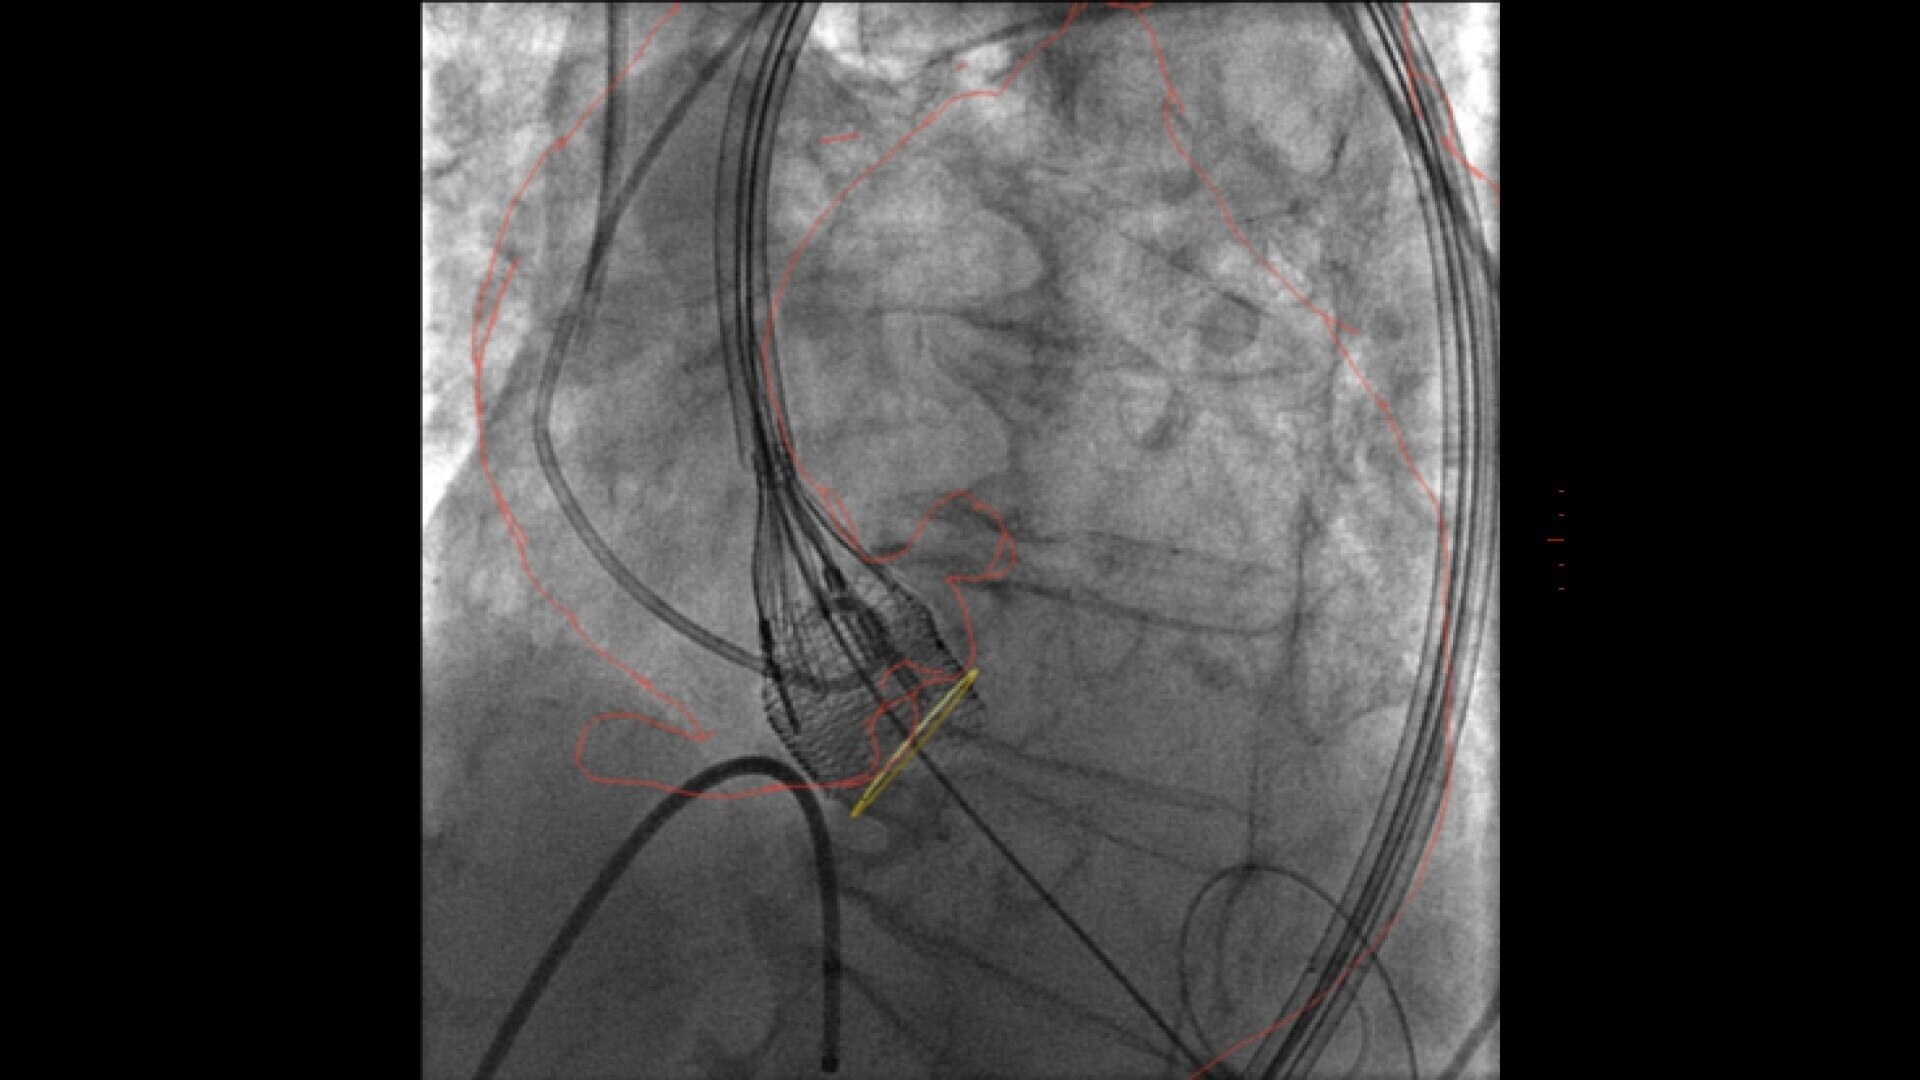

GUIDE

3D fusion helps guide each step with confidence, from the trans-septal puncture to the device deployment. Significantly reduce procedure time, while decreasing contrast media and dose.

ASSESS

Once the device is deployed, employ echocardiography to confirm the device location and evaluate compression before releasing the device⁴.

With Valve ASSIST 2, improve your patient outcomes in LAAC⁵:

• 78% reduction in volume of contrast media

• 28% reduction in procedure time

• 25% reduction in fluoroscopy time